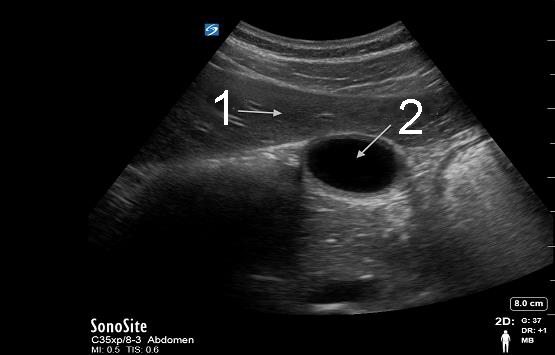

Gallbladder Transverse Image

Liver

Gallbladder